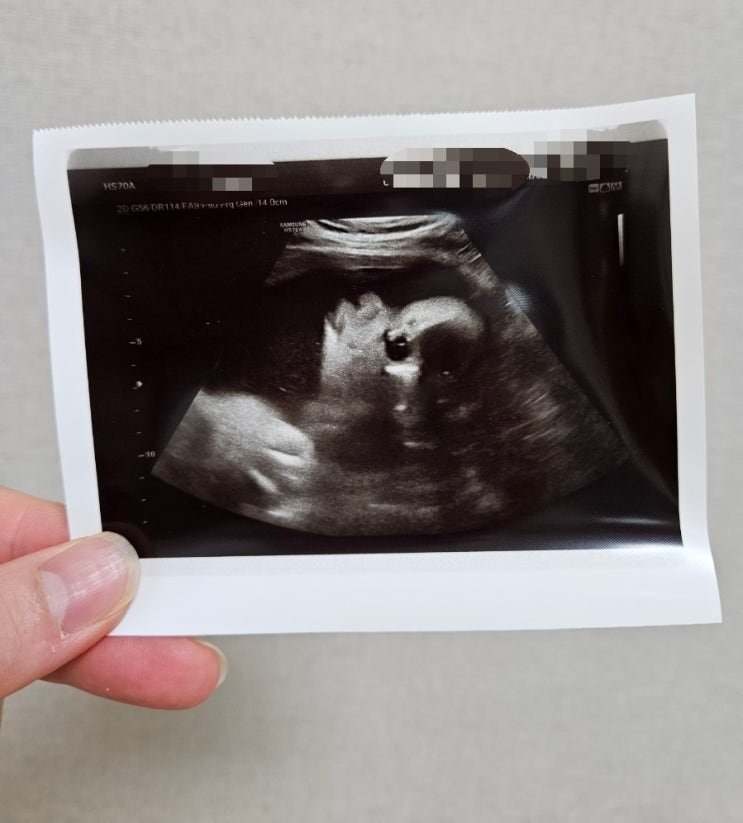

30주차 산부인과 정기검진, 33주차 태동검사 및 배 크기

안녕하세요~^^ 롱다리콩순이 입니다~♡ 오늘은 오랜만에 우리 아기천사 햇님이 이야기로 찾아왔어요~^^ 202...